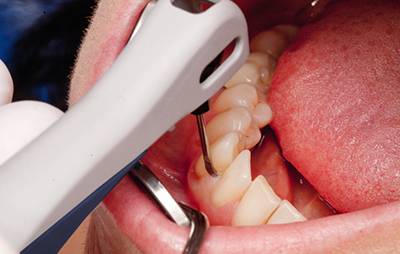

Обязательно измеряют глубину зазора между десной и зубом. Такая несложная процедура помогает определить масштаб поражения. Для этого применяют пародонтальную пробу, которая помещается между зубом и десной. Таким способом обследуют каждый зуб, а совокупность результатов даёт пародонтограмму.